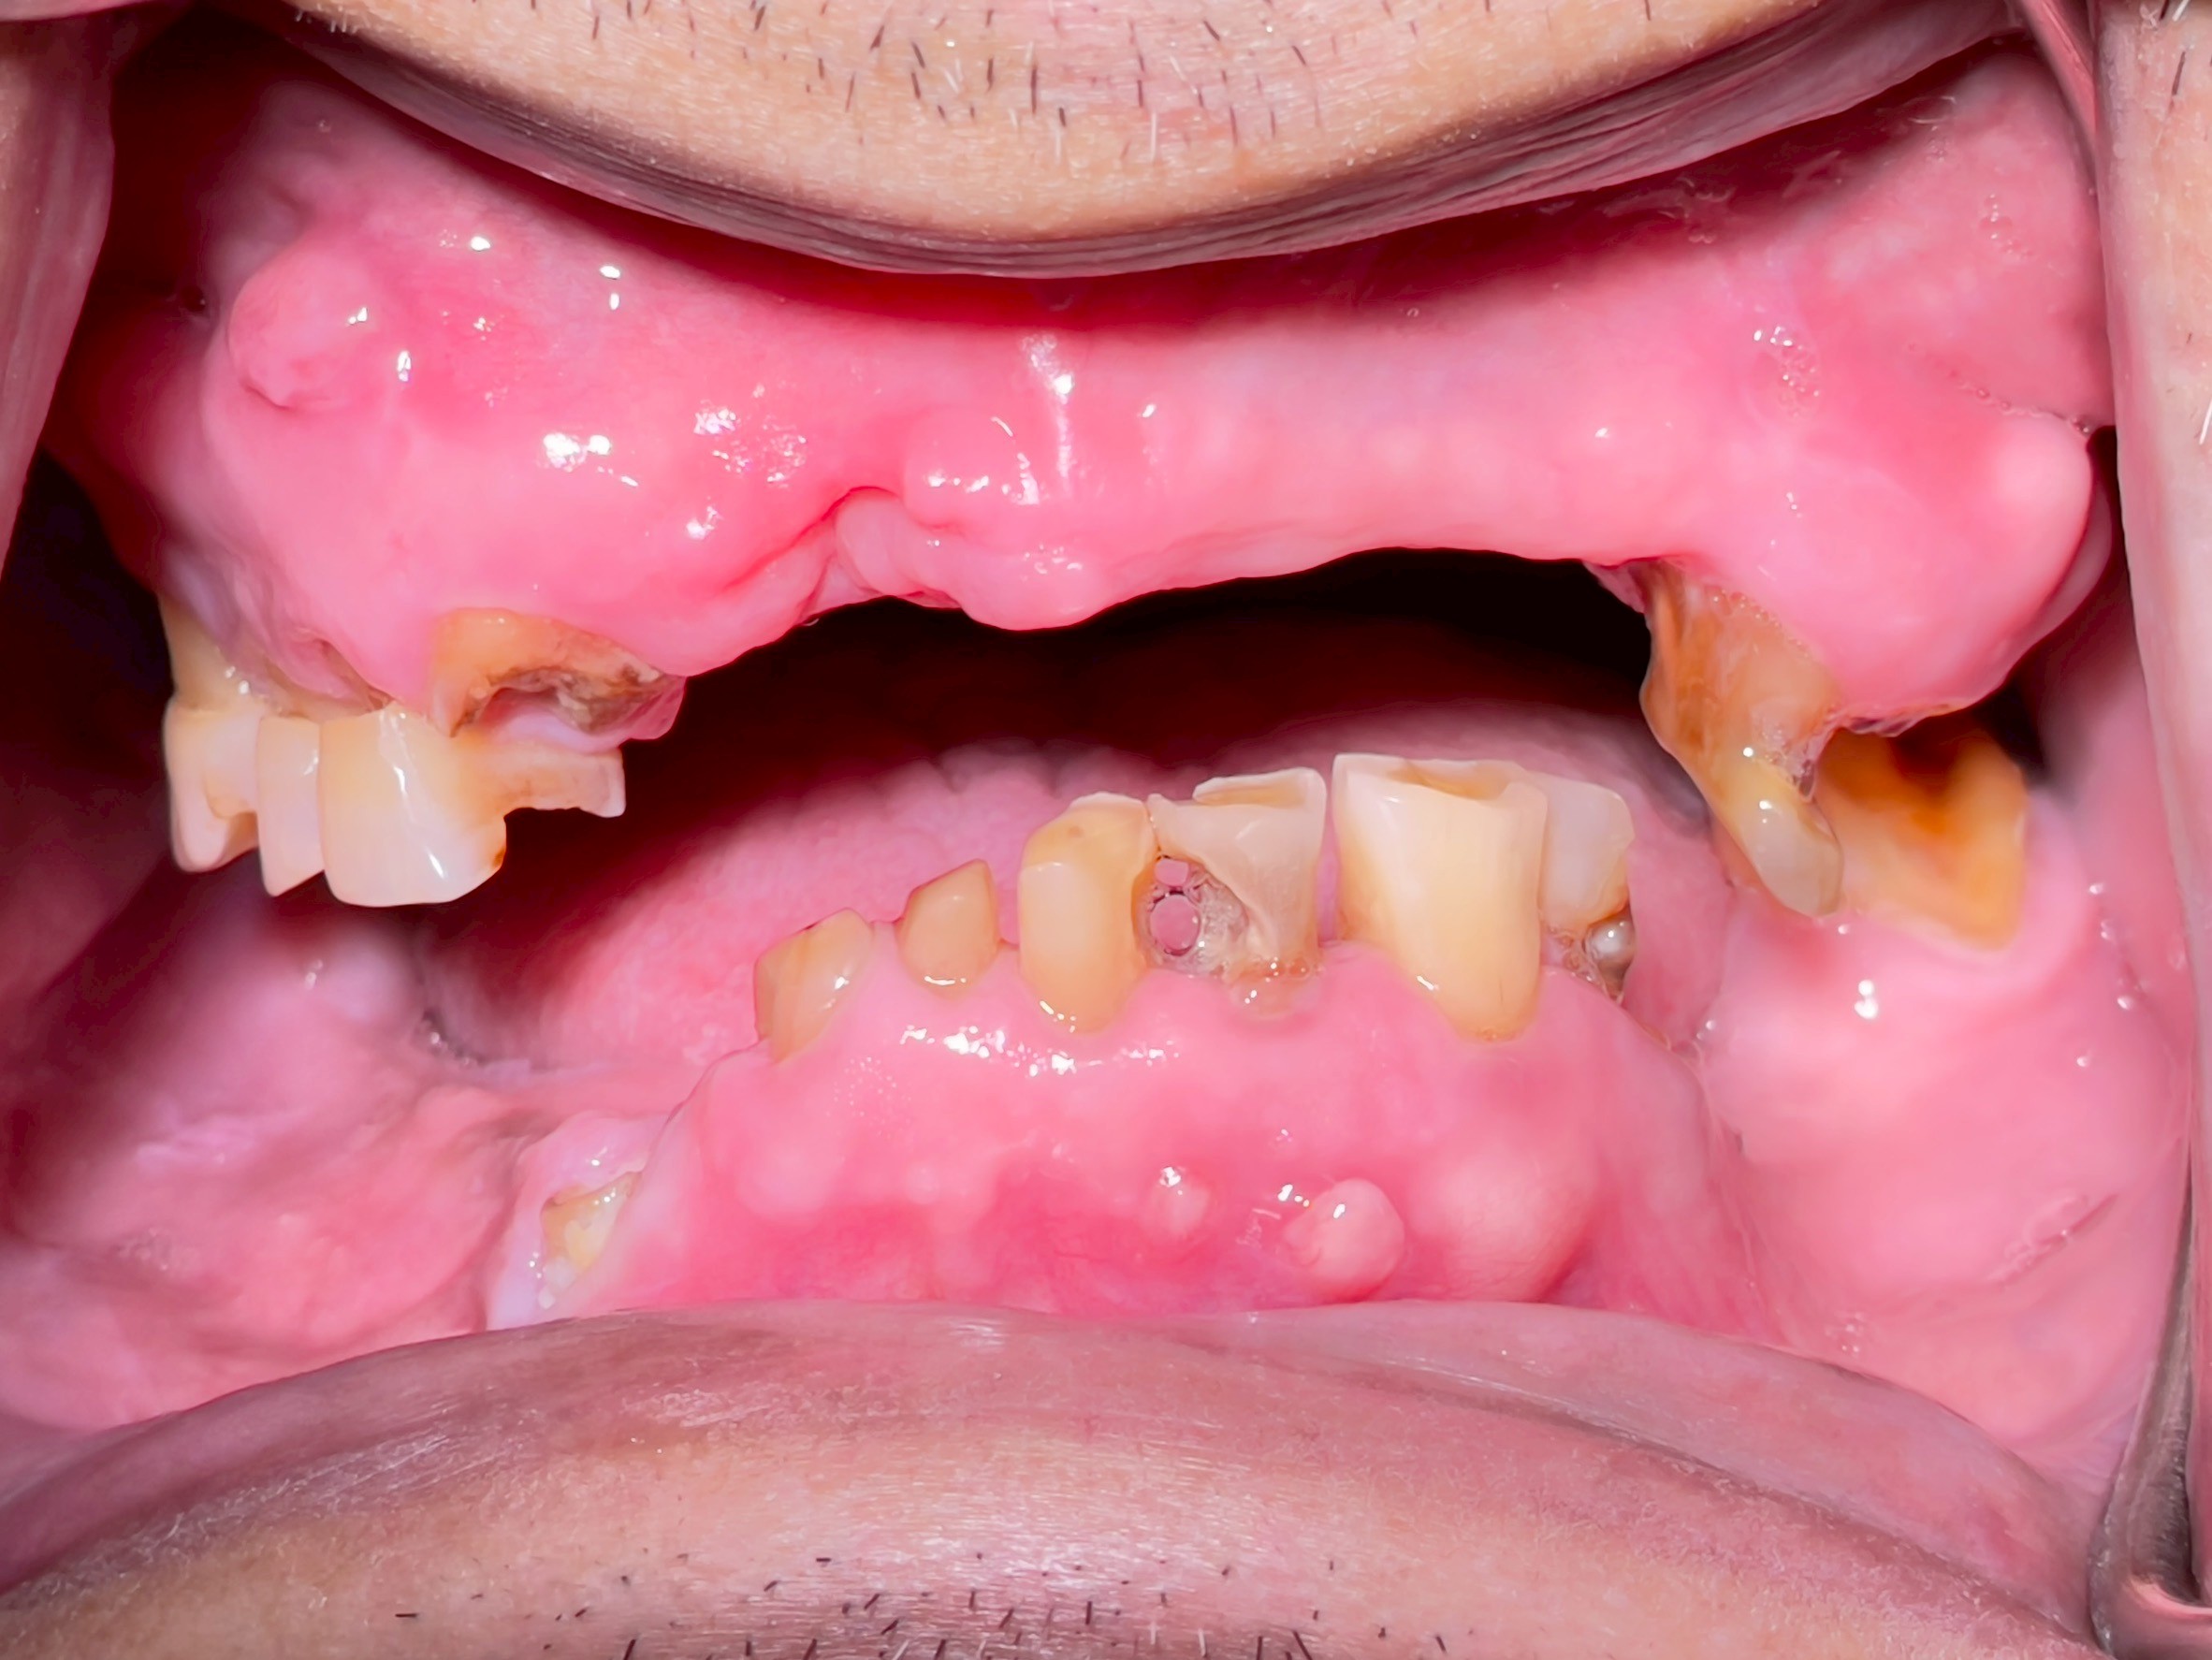

All-on-4 Implants Lower Jaw + Partial Denture Upper Jaw